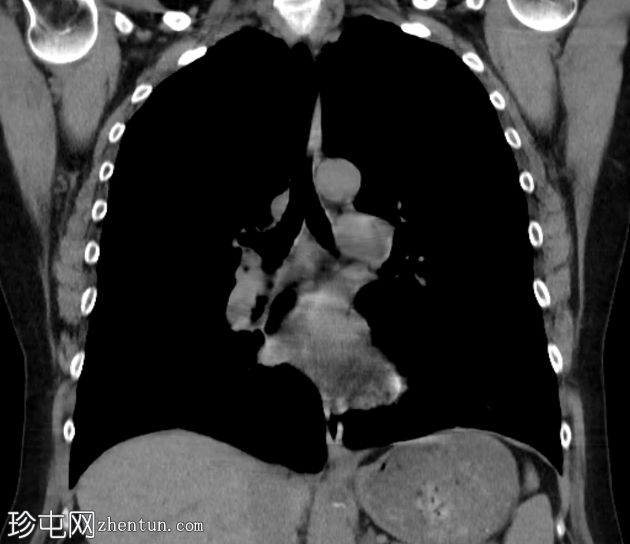

肺窗

冠状

非造影

双侧肺(尤其是上叶)广泛融合性小叶中心型肺气肿。

左上叶肺瘢痕形成,可能是先前感染的后遗症。

双侧乳房植入。

小叶中心型肺气肿是最常见的肺气肿形态学亚型。

早期小叶中心性肺气肿通常表现为小(<1 mm 至 3 cm)、圆形、均匀分布、边界不清的透亮区,可能出现在小叶中心动脉周围的次级肺小叶中央部分,而在严重的情况下,低衰减区会融合且不可分离,并且失去小叶中心分布。